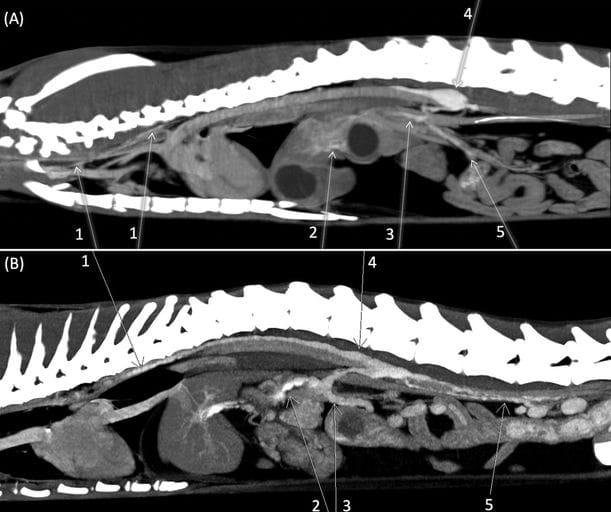

F I G U R E 1 Sagittal reconstruction from delayed post-contrast intravenous series showing diffuse enhancement of the lymphatic system in two feline patients (A, B). A, Images acquired with 16-row MDCT unit (Siemens Emotion 16) (Slice thickness 1,5 mm; WW 402; WL 109). 1- thoracic duct; 2- hepatic lymph vessels; 3- celiac trunk; 4- cisterna chyli; 5- mesenteric lymph vessels. B, Images acquired with Dual-source CT 192 × 2(Siemens Somatom Force) volume rendered (Slice thickness 0,6 mm; WW 300; WL 40). 1- thoracic duct; 2- celiac trunk; 3- mesenteric trunk; 4-cisterna chyli; 5- lumbar trunks.